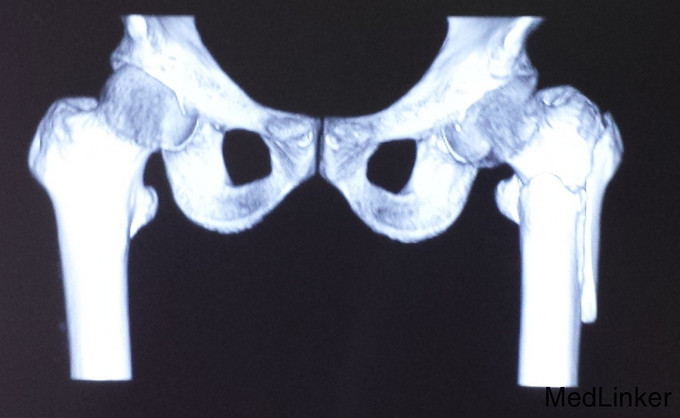

患者,男性,75岁,意外摔倒。右腿活动受限1小时入院。

X光片提示,患者在摔倒时,右腿发生了粗隆间合并粗隆下骨折。各项指标均符合,先进行了两天的静脉消炎注射,第三天进行了手术,手术顺利。